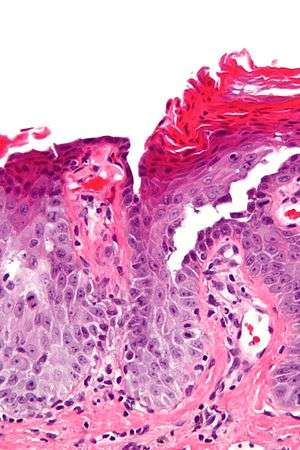

| Micrograph of transient acantholytic dermatosis, showing subcorneal separation and acantholysis. H&E stain. | |

Grover's may be suspected by its appearance, but since it has such a characteristic appearance under the microscope a shave skin or punch biopsy is often performed.